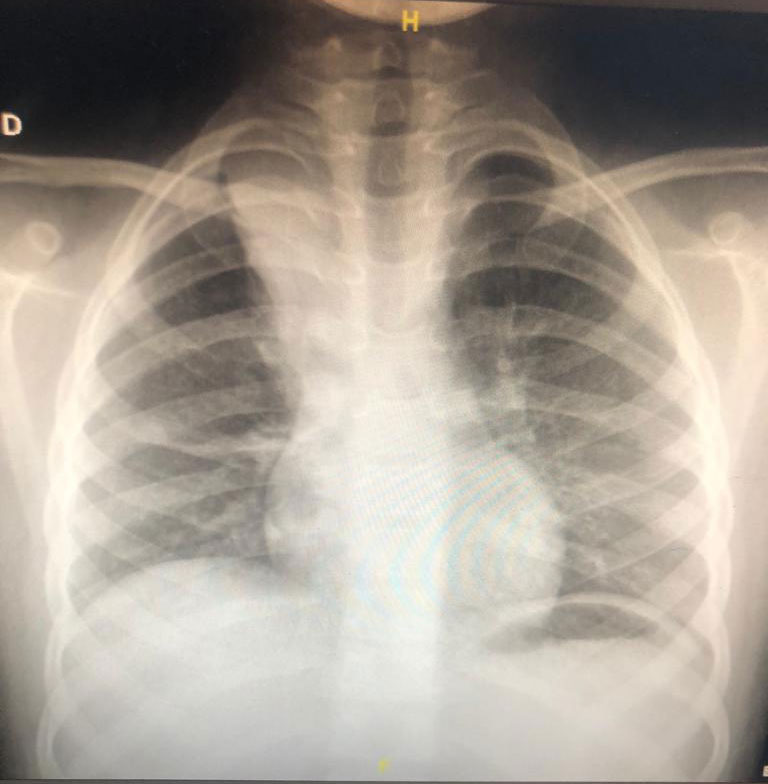

Pneumonias

Pneumonia é uma palavra grega que significa “inflamação dos pulmões”. Trata-se de doença do trato respiratório inferior geralmente causada por vírus, bactérias, fungos ou inalação

Atelectasia

Você sabe o que é atelectasia? Já ouviu falar? É o termo para designar o colapso ou perda de volume pulmonar. A atelectasia pode afetar